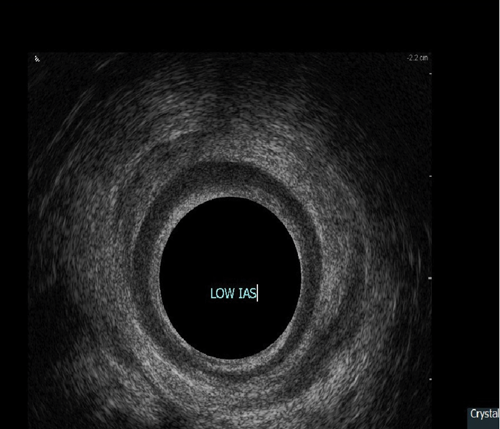

Endoanal ultrasound

This procedure is indicated for assessment of the anal sphincter in patients with incontinence. This allows evaluation of the internal and external anal sphincters (sphincter thickness, length and scarring). It is pertinent to obtain history of obstetric trauma as well as any surgeries / intervention to aid assessment.

As with the proctogram technique, the procedure is explained in detail and consent obtained prior, and the presence of a chaperone makes the patient more comfortable. Digital rectal examination is performed as a reference to assess anal tone. Still images as well as cine of the ultrasound are taken to assess the sphincter complex (Figure 3).

Figure 3a: (Top, middle and bottom) Normal endoanal ultrasound.

Figure 3b: Abnormal / deficient low internal anal sphincter.

Figure 3c: High External anal sphincter scars due to obstetric trauma.